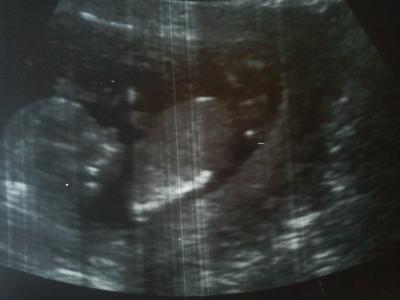

huhu, nach 5 langen Wochen hatte ich heute endlich mal wieder einen FA-Termin. Meine Ärztin hat sich viel Zeit genommen. Da ich das Ersttrimesterscreening nicht machen lassen werde, hat Sie sich die Nackenfalte mal so angesehen und meinte, es wäre alles unauffällig. Unser Krümel hat sich kräftig bewegt und uns auch mal zugewunken. Mein Freund war diesmal auch dabei und ganz überrascht, dass das Kleine schon so aktiv ist Ich bin so froh, dass alles in Ordnung ist, man hört hier in letzter Zeit ja so viel Schlimmes. Ein Bild hab ich natürlich auch noch bekommen

Bild zu Heute endlich wieder FA-Termin - Forum für Januar - Mamis